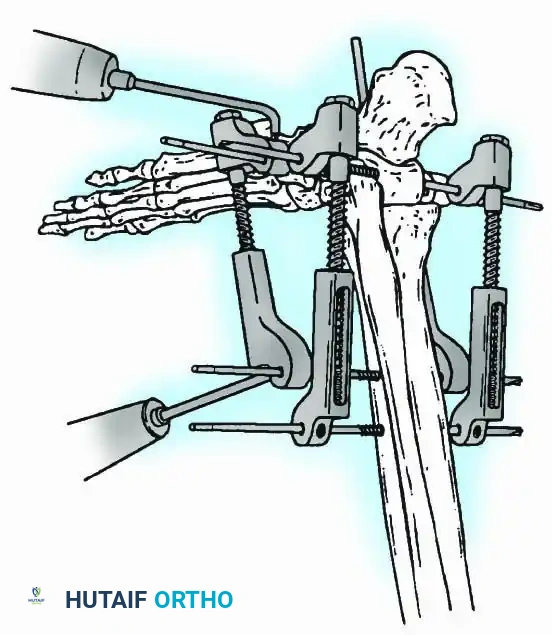

External Fixation

Historically pioneered by Charnley, external compression arthrodesis utilizes pins placed through the distal tibia and the body of the talus. Because Charnley's original uniplanar device lacked rotatory stability, Calandruccio designed a triangular frame to control motion in all three planes while applying massive compression.

Modern iterations, such as the Calandruccio II compression device, offer greater latitude in pin placement to avoid compromised skin. Ring or circular external fixators (Ilizarov, Taylor Spatial Frame) are the gold standard for salvage situations, including active infection, massive bone loss, or failed TAA, as they allow for simultaneous compression, deformity correction, and early weight-bearing.